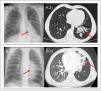

Caso 1. Varón de 8 años, sin antecedentes de interés, que presenta tos productiva de un año de evolución con atelectasia crónica del lóbulo inferior izquierdo (LII) en radiografías (RX) de tórax y bronquiectasias con engrosamiento mural y contenido mucoso en tomografía computarizada (TC) pulmonar (fig. 1). Se realiza broncoscopia flexible visualizando cuerpo extraño (CE) intrabronquial en LII que se extrae en el mismo procedimiento (fig. 2, vídeo), resultando ser una cáscara de pipa.

A.1) Caso 1. Radiografía de tórax con atelectasia de lóbulo inferior izquierdo (flecha roja). A.2) Caso 1. Tomografía computarizada con bronquiectasias en lóbulo inferior izquierdo (flecha roja). B.1) Caso 2. Radiografía de tórax con infiltrado paracardíaco izquierdo (flecha roja). B.2) Caso 2. Tomografía computarizada con atelectasia de língula y bronquiectasias (flecha roja).

Caso 2. Varón de 2 años, previamente sano, con súbita hemoptisis mientras saltaba en una cama elástica. En RX de tórax presenta infiltrado paracardíaco izquierdo y en TC pulmonar lesión «mal definida» en bronquio principal izquierdo con atelectasia de língula y bronquiectasias (fig. 1). En broncoscopia flexible se visualiza CE con importante edema e inflamación de mucosa adyacente, imposibilitando su extracción (fig. 2). Tras corticoterapia y antibioterapia intravenosa, se extrae mediante broncoscopia rígida, hallando una rama vegetal.